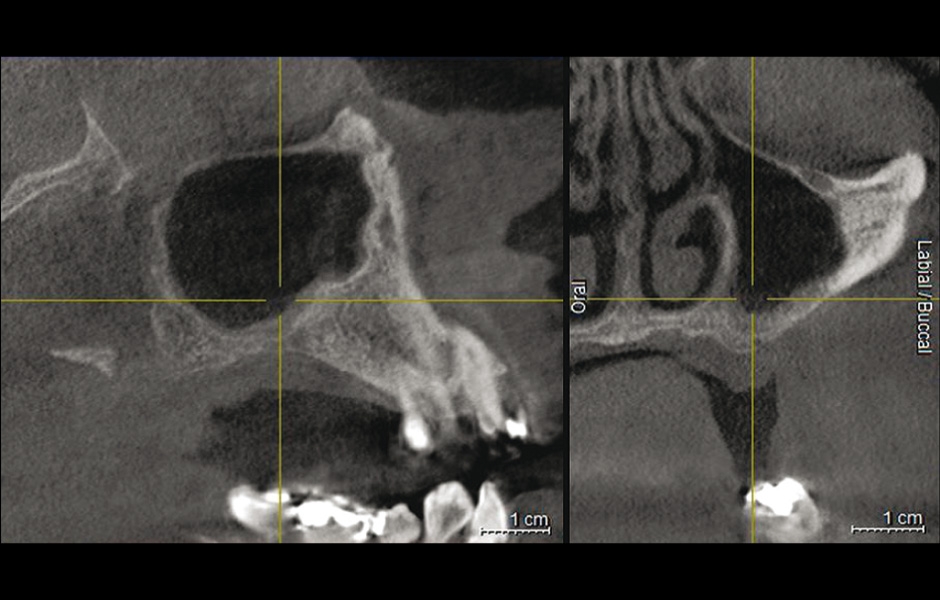

Obr. 6: CBCT po 10 letech od augmentace a zavedení implantátů ukazuje oblast bez recidivy.

Do studie bylo zařazeno 10 pacientů s aspergilózou maxilárního sinu. U všech pacientů byl na panoramatických snímcích i na CBCT patrný radiopakní stín. CBCT navíc ukázalo, že čelistní dutina byla kompletně vyplněna homogenní patologickou masou. Chirurgická léčba sinu byla provedena za antibiotické profylaxe (Amoxicillin 2 g/den po dobu 7 dní) a intravenózní sedace (Midazolam). Kostní okénko bylo vytvořeno mikropilkou (DENTSPLY Implants), umožnilo bezpečný přístup do sinu. Po odklopení separovaného kostního fragmentu byla aspergilóza spolu s cizorodým materiálem kompletně odstraněna a dutina vypláchnuta peroxidem vodíku (H₂O₂ 3 %). Pro dodatečnou dezinfekci byla použita fotodynamická dekontaminace laserem HELBO (HELBO, Bredent Medical GmbH). Na závěr zákroku byla kostěná lamela vrácena zpět jako biologický uzávěr sinu a fixována resorbovatelnými stehy. Histopatologické vyšetření ve všech případech potvrdilo infekci aspergilózou. Po třech měsících, kdy CBCT potvrdilo nepřítomnost sinusové patologie a průchodné ostium, byla provedena augmentace kosti. Kostní bloky byly odebrány z retromolárové oblasti mandibuly a přeneseny ve 3D konfiguraci podle split-bone block techniky v kombinaci se sinus liftem. Sinus byl augmentován autologní kostí a biomateriálem (FRIOS Algipore®, DENTSPLY Implants) vrstvenou technikou. Po dalších třech měsících byly do augmentované oblasti zavedeny implantáty. O další tři měsíce později byly implantáty odhaleny a následně byla zhotovena definitivní protetická náhrada.“

U všech 10 pacientů proběhla chirurgická léčba aspergilózy bez komplikací, což umožnilo provedení následných augmentačních výkonů. Všechny kostní a sinusové štěpy se zhojily bez obtíží. Do augmentované oblasti bylo tři měsíce po operaci úspěšně zavedeno celkem 26 implantátů, které byly proteticky ošetřeny podle stanoveného protokolu. Pacienti dodržovali přísný šestiměsíční recall systém a byli průběžně sledováni až 10 let, v průměru po dobu 78 měsíců. Implantáty vykazovaly dobrý stav, hloubka sondáže nepřesáhla 4 mm. Pooperační radiologické snímky neprokázaly žádné známky další sinusové infekce.